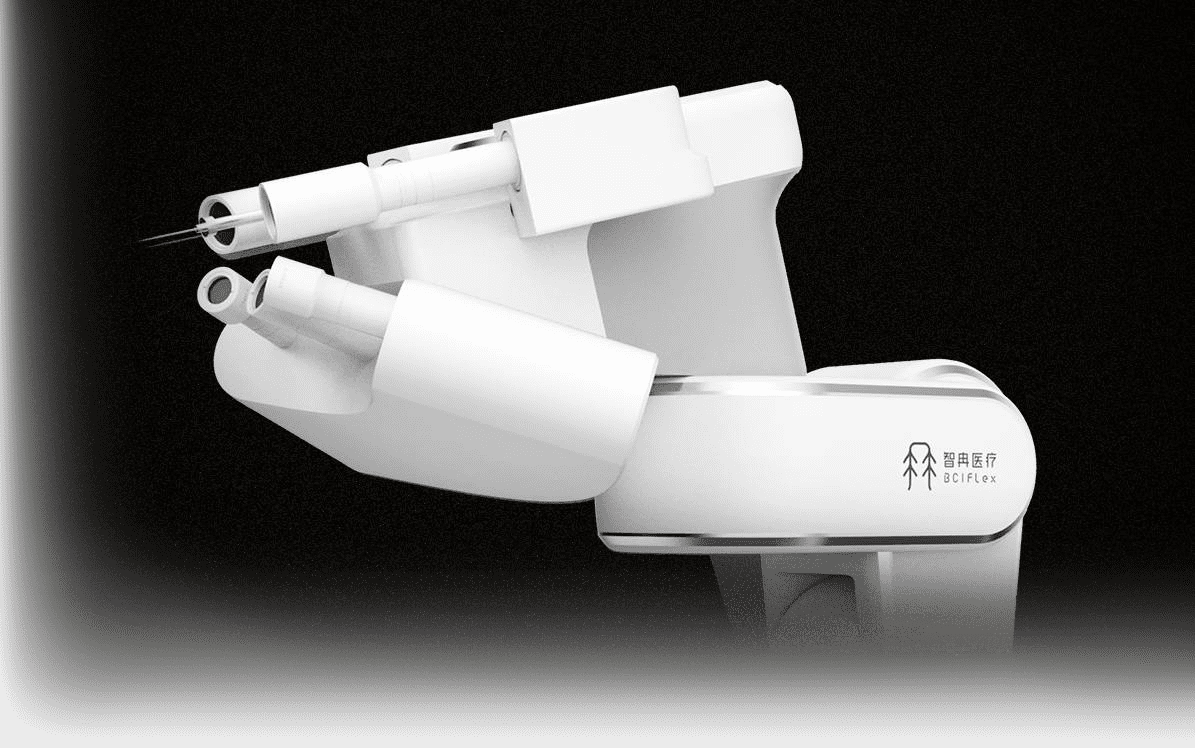

基于“视觉伺服”技术的高精度运控平台,搭载多组高清相机,实现快速、精准定位目标。结合智能运控算法,其定位精度可达细胞级别。

自动规划电极植入位置与深度,智能规避血管等危险区域,实现电极植入的全程智能化、自动化。

单根电极丝植入时间不到30秒,并可连续植入多根电极丝,半小时内,即可完成千通道电极的植入,大幅提升手术效率。